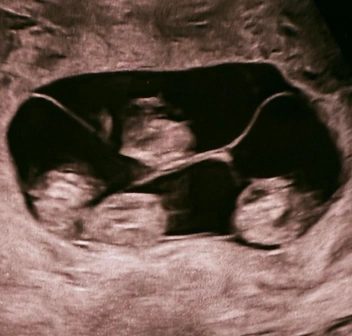

В 17-м роддоме в Санкт-Петербурге произошло уникальное событие, — сообщает Фонтанка.ру. Одна из его пациенток родила сразу четырех девочек, причем все они — однояйцевые близнецы. Ранее в России такие случаи не регистрировали.

По словам заместителя главного врача родильного дома № 10 и профессора Евгения Михайлина, который также консультировал петербурженку, монохориальная — «однояйцевая» четверня — 1 случай на 15,5 миллиона родов. Вес новорожденных составил от 1360 до 1640 граммов, а рост — от 37 до 41 сантиметра. Для срока в 32 недели это очень хорошие показатели — говорят специалисты.

По данным медиков, в мире известно всего около 15 случаев рождения четверняшек-близнецов, и в 10 из них рождались девочки.